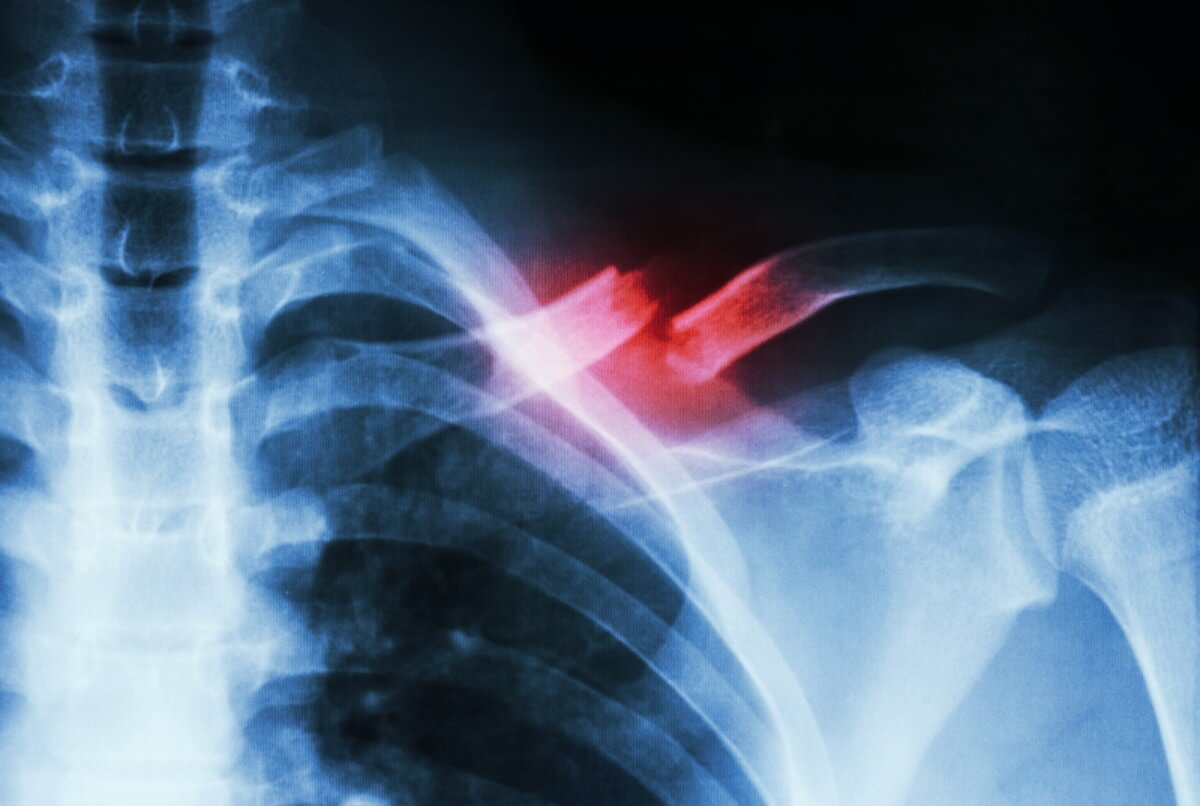

Экспериментальное лечение может помочь в несколько раз быстрее срастить сломанные кости

Многие из вас могут знать на своем опыте о том, насколько долгим и неприятным может показаться процесс заживления кости, сломанной в результате падения или сильного удара. К счастью для спортсменов, спасателей и других представителей профессий, чьи будни связаны с повышенным риском травматизации, новое исследование, опубликованное на портале newatlas.com, показало, что комбинация, состоящая всего лишь из двух препаратов, может ускорить высвобождение стволовых клеток из костного мозга, тем самым увеличив скорость восстановления целостности костной ткани в несколько раз.

Новое экспериментальное лечение может помочь при лечении костных повреждений